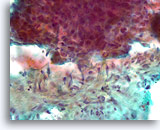

Proliferatieve ductale laesie, Borst FNA, Directe uitstrijk.

Bij een sterkere vergroting kan men door van boven naar beneden te focussen enkele vermoedelijke myoepitheliale cellen zien die vermengd zijn met de ductale cellen en vermoedelijke spleetachtige ruimten. Deze twee kenmerken zijn kenmerkend voor ductale hyperplasie van het gewone type, een laesie die ruwweg een tweevoudige toename in het relatieve risico van borstkanker vertegenwoordigt.[14].

Proliferatieve ductale laesie, Borst FNA, Directe uitstrijk.

Bij een sterkere vergroting kan men door van boven naar beneden te focussen enkele vermoedelijke myoepitheliale cellen zien die vermengd zijn met de ductale cellen en vermoedelijke spleetachtige ruimten. Deze twee kenmerken zijn kenmerkend voor ductale hyperplasie van het gewone type, een laesie die ruwweg een tweevoudige toename in het relatieve risico van borstkanker vertegenwoordigt.[14].